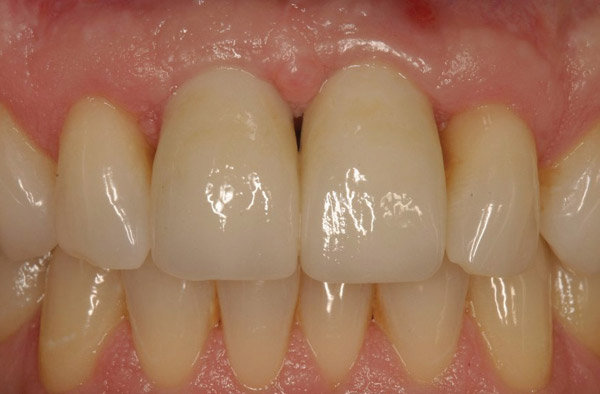

Figure 12  Buccal view of the implants immediately after provisionalization. Even at the temporary stage, the soft tissue closely mimicked the original periodontal drape.

Figure 12

Figure 13  Initial view of this patient depicts the esthetic disharmony and smile imbalance. There was a retained primary maxillary canine on the right, a permanent canine in place of the right lateral incisor, a missing tooth No. 10 replaced with a cantilever restoration, asymmetric gingival margins, recession on tooth No. 11, and uneven incisal edges.

Figure 13